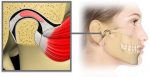

Smilkininio žandikaulio sąnario sutrikimai, literatūroje sutrumpintai vadinami TMJ sindromu (angl. temporomandibular jaw disorders arba TMJ sindrome) TMJ sindromas pasireiškia skausmas smilkininio žandikaulio sąnario plote. Šis sąnarys jungia apatinį žandikaulį su smilkininkauliu, abiejuose galvos pusėse. Pridėjus pirštą greta ausies, žiojantis galima pajusti šio sąnario judėjimą. Sąnarys leidžia judinti apatinį žandikaulį kramtant ir kalbant. TMJ sindromas nėra […]